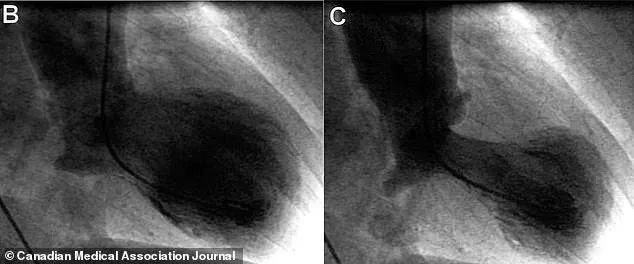

Diagnosing broken heart syndrome is a meticulous process of elimination. Because its symptoms mirror those of a heart attack, doctors initially assume the worst. An echocardiogram (EKG) is used to capture live images of the heart, revealing a distinctive 'takotsubo' shape — the bottom of the heart's main pumping chamber balloons outward while the base remains narrow, resembling a Japanese octopus trap. Blood tests also check for elevated troponin levels, a protein released when heart muscle is damaged. However, the definitive test to rule out a heart attack is a cardiac catheterization, where dye is injected into the coronary arteries to detect blockages. Clear results confirm the diagnosis of takotsubo cardiomyopathy.